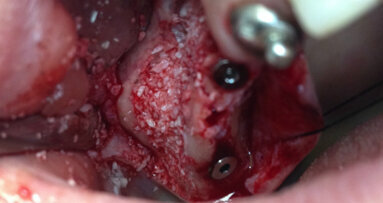

Chirurgia

Prima di estrarre gli incisivi, le corone 13 e 23 sono state rimosse e i denti sono stati preparati per l’applicazione di un ponte provvisorio. Con una ceratura sul modello della situazione e sui pontic, è stata creata una forma ottimale per supportare e modellare il tessuto mole durante la fase di guarigione. Nello stesso tempo, il ponte provvisorio funziona come copertura della ferita se non è possibile la chiusura primaria (Figg. 3-6)1-4. Nella fase successiva, i denti da 12 a 22 sono stati estratti. Il contorno del lembo risparmiava la papilla mediana e quella mesiale su 12 e 22. A causa dei difetti ossei interprossimali, lo scollamento della papilla in questa regione avrebbe portato a gravi recessioni. I difetti ossei verticali, soprattutto tra 11 e 12, erano ovvi dopo lo scollamento del lembo a tutto spessore. Sono state eseguite incisioni di rilascio distalmente ai canini e solo nella gengiva aderente per evitare la formazione di cicatrice attraverso tagli verticali nella mucosa. Il vestibolo basso rendeva meno logico uno lembo a spessore parziale o a tasca periostale. Mobilizzando il tessuto molle dalle labbra mediante altri design di lembo porterebbe a limiti funzionali, tensione della sutura e plastica gengivale secondaria per riposizionare il tessuto molle coronale tras-posizionato. I margini della ferita sono stati ridefiniti per rimuovere l’epitelio prolungato e i difetti ossei liberati dalla crescita interna del tessuto molle (Figg. 7-10). La perdita di osso orizzontale era moderata. Gli impianti sono stati posizionati leggermente sottocrestali. Sebbene il gap tra gli impianti e il piano buccale fosse circa 1-1,5 mm e lo spessore del piano buccale 1-1,5 mm a causa del riassorbimento, abbiamo optato per impianti 3,8 mm, lasciando un gap di 1,5 mm al piano buccale5-10. Lo spazio interimplantare e il piano buccale sono stati incrementati con una combinazione di alloinnesto e xenoinnesto. Lo xenoinnesto è stato applicato anche sul piano buccale, in modo da manipolare il riassorbimento del piano buccale. Come barriera è stata utilizzata una membrana di pericardio (Fig. 11). L’anatomia dell’arcata superiore e il vestibolo basso non permettevano una chiusura primaria. Per proteggere la membrana dal riassorbimento proteolitico e l’incremento, abbiamo applicato due strati di tessuto sulla membrana. Attraverso lo strato di collagene e la protezione del ponte provvisorio, dopo due settimane ci si aspettava granulazione libera della copertura dell’alveolo estrattivo (Fig. 12)11,12.